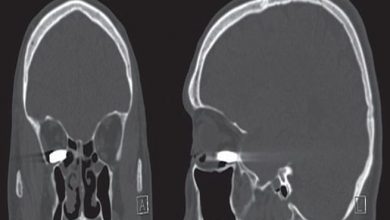

معجزة طبية .. رجل أمريكي ينجو من الموت بعد استقرار رصاصة في عينه